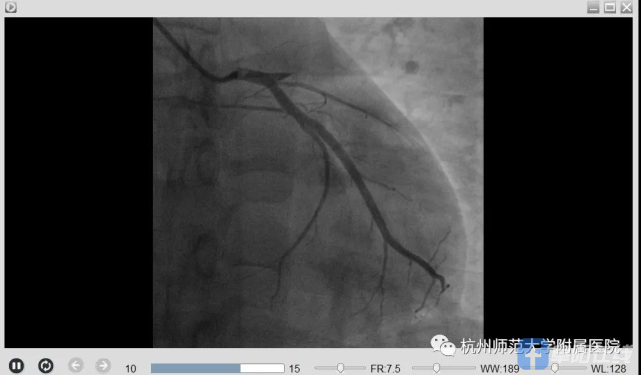

刘主任立刻启动胸痛中心绿色通道,通知患者家属后,刘主任带领胸痛团队立即将患者送至导管室,经过冠脉造影证实,患者前降支血管(为心脏收缩的主要功能血管)完全闭塞,符合De-Winter综合征的表现,立即予以开通闭塞的血管,植入支架1枚,小方心脏血管血流恢复,胸痛症状明显缓解,血压心率逐渐平稳下来。

手术前后对比图